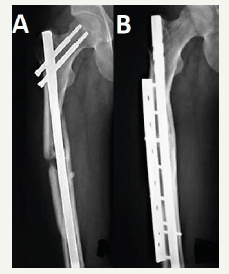

Weresh et al. [10] suggested the re-evaluation of routine exchange nailing which was considered as the gold standard technique to treat non-union after femur fracture nailing, as union obtained in only 53% of the patients received exchange nailing in their series, with a significant number of patients required additional procedures to achieve fracture healing. Heng et al. [9] in 1997 recognised that residual instability in diaphyseal femur fracture treated with IMN is the leading cause for non-union, so they got the idea to apply an “augmentative” plate (Figure 1) keeping the nail in situ in a series of 17 non-united femoral fractures that were primarily treated with IMN, they reported 100% fracture union at a mean time of 7 months without complications, and concluded that plate augmentation provided mechanical stability which resulted in fracture union.

Figure 1:A. Non-union fracture femur after IMN; B. Follow up x-ray after 7 months of treatment with augmentation plate.